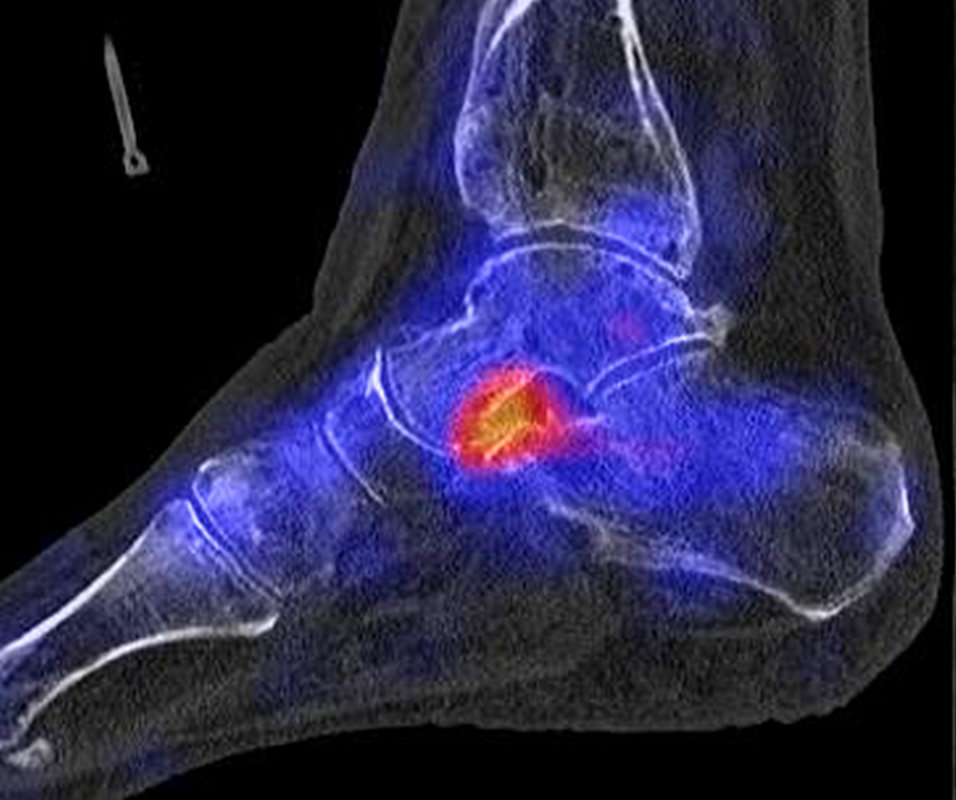

In Abbildung 3.4. ist ein typisches Beispiel für ein symptomatisches Os trigonum dargestellt.

Zum Lesen der Bildbeschreibung und zur Vollansicht bitte das Bild anklicken. Bild: H. C. Rischke

Bei der Differenzialdiagnose von Impingement-Syndromen am Sprunggelenk kann das SPECT/CT den Ort der Symptome- verursachenden Stressreaktion darstellen 32. Eine typische Ursache für ein posteriores Impingement kann ein Os trigonum sein. Scherkräfte im Bereich der Synchondrose eines Os trigonum lösen hypermetabole Stressreaktionen aus. Die Exzision des Os trigonum stellt eine erfolgreiche Therapie dar, sodass der Befund eines szintigraphisch aktivierten Os trigonum den Erfolg einer chirurgischen Therapie vorhersagen kann 3334.